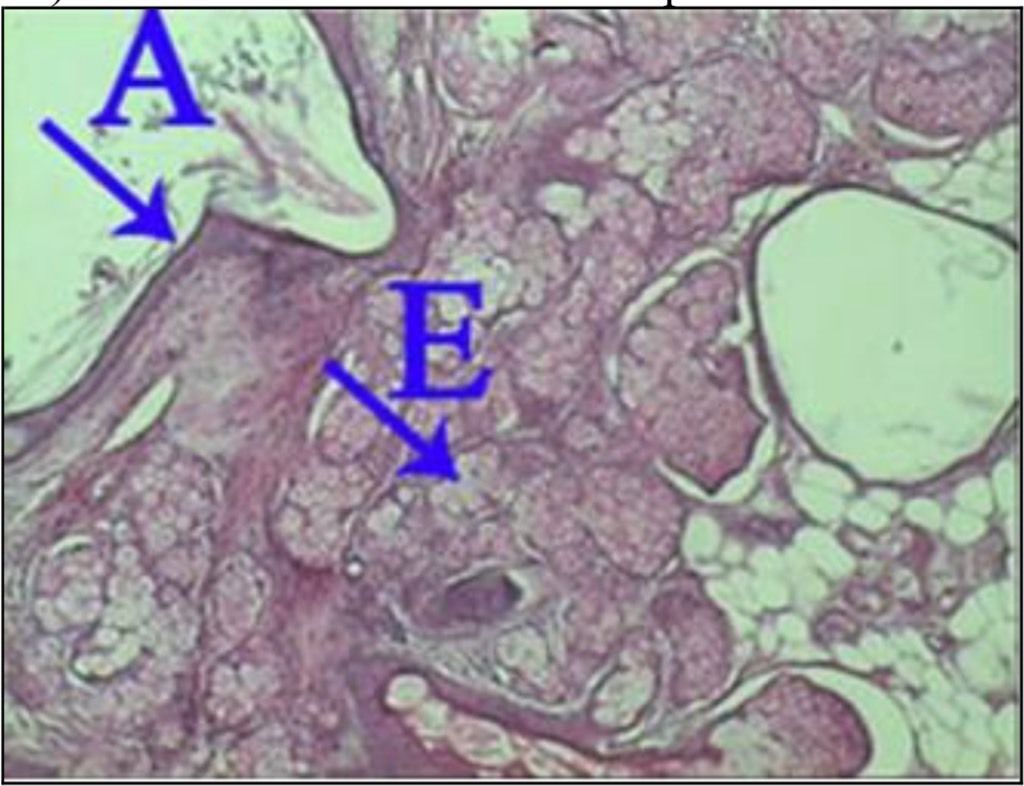

Question 51

Question

What is the correct answer at point A?

Answer

• - lobule adénomateux

• - prolifération épithéliale canaliculaire

• - prolifération conjonctive nodulaire

• - stroma myxoïde et fibreux

• - canaux galactophores étirés et aplatie

Question 52

What is the correct answer at point B?

Question 53

What is the correct answer at point C?

Question 54

What is the correct answer at point D?

Question 55

What is the correct answer at point E?